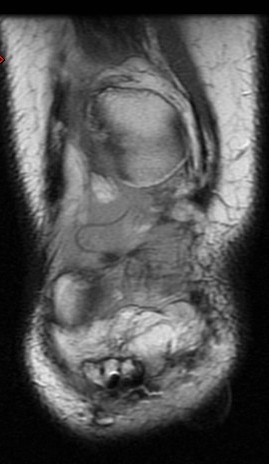

27 y/o patellar tendon rupture with repair 2 years ago. Re-injury 1 year ago. Now with increasing pain and limited range of motion.

Figure 4 for case Patellar tendon re-tear

Figure 4

The acute changes have resolved but the patient has a re-tear of the tendon. The patella is retracted superiorly. Important to measure the length of gap as well as any residual tendon for surgical planning.

Patellar tendon re-tear